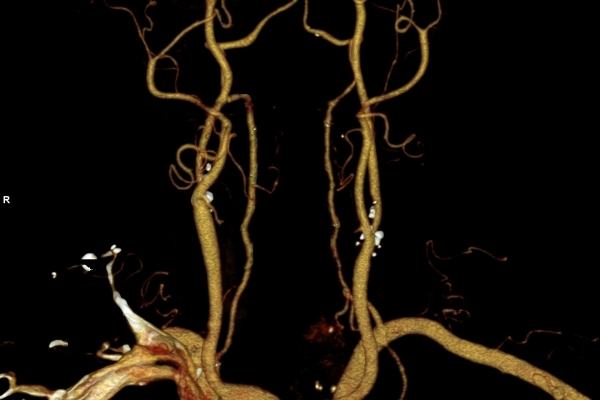

Modernste Bildgebung für jeden Bereich Ihres Körpers

Entdecken Sie, welche CT- und MRT-Untersuchungen in unserer Radiologie für jeden Bereich Ihres Körpers möglich sind.

• Gefäßdiagnostik (CT-Angiographie)

Wir bieten ein breites Spektrum an Untersuchungen an, von Standarduntersuchungen der Gelenke, Organe oder großflächigen Körperregionen bis zu Spezialuntersuchungen zum Beispiel des Herzen oder der Gefäße. Zusätzlich werden Angiographien (Darstellung von Blutgefäßen), Endometriose-Abklärungen und Mamma-Untersuchungen durchgeführt. Genauere Details können Sie der MRT/CT-Übersicht und der Preisliste entnehmen, oder Sie wenden sich direkt an unser Team, das Sie gerne zur passenden Untersuchung berät.